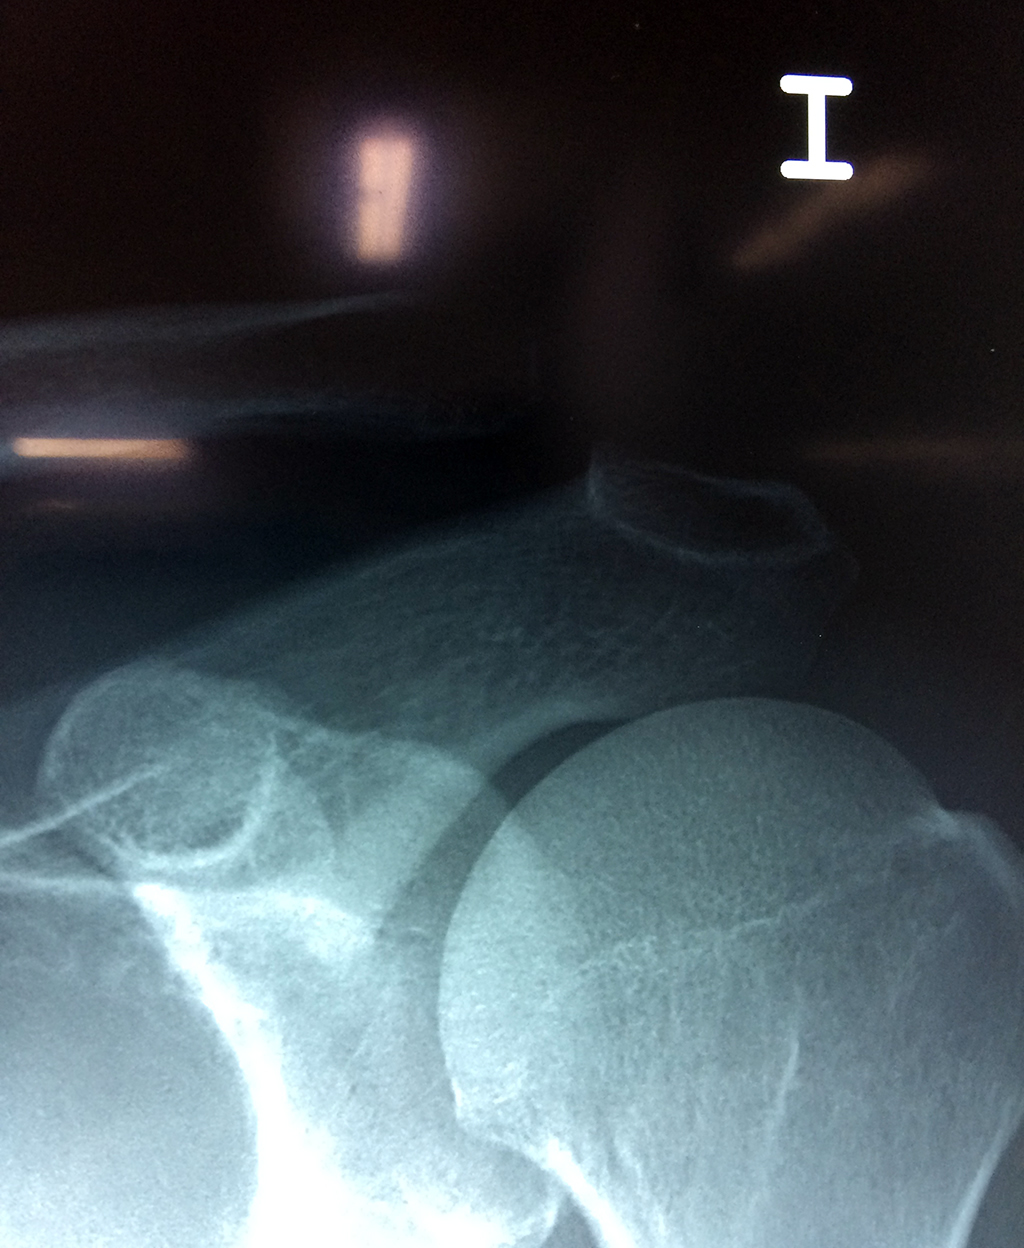

Calcaneo - Clavícula

La clavícula es un hueso largo, con forma de "S" itálica, situado en la parte anterosuperior del tórax. Junto con la escápula forman la cintura escapular. Se puede palpar por toda su longitud y se extiende del esternón al acromion de la escápula, siguiendo una dirección oblicua lateral y posterior.